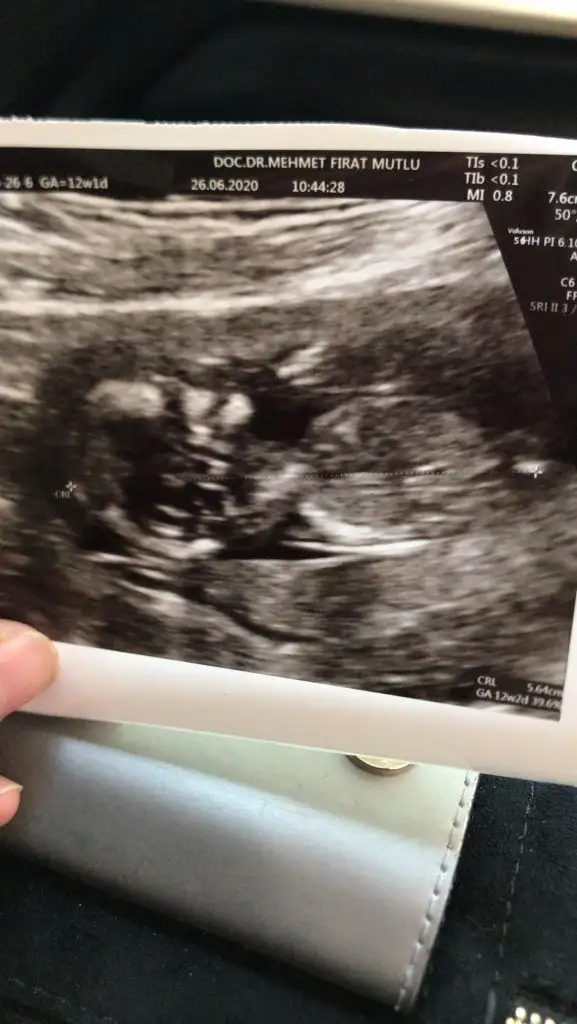

Kızlarr selam bende cinsiyet tahmini alabilir miyim😍

Eklentiler

• 91B2775E-DAD5-468E-9AA1-CF97C6A6E882.webp

91B2775E-DAD5-468E-9AA1-CF97C6A6E882.webp

31,5 KB · Görüntüleme: 53